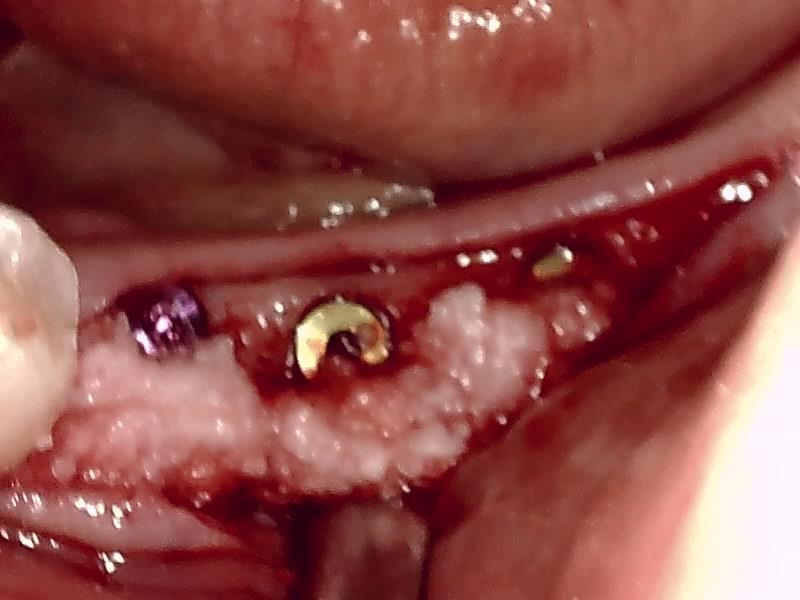

歯肉切開してヒーリングアバットメントの装着している状況です。

ヒーリングアバットメント装着して歯肉を縫合する。